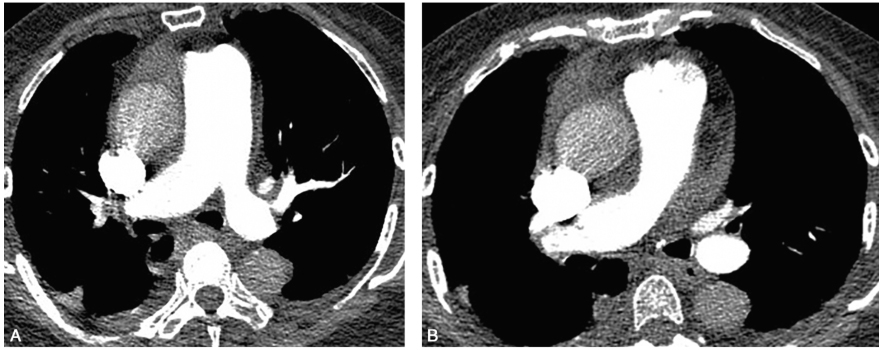

出院3周后复查肺动脉CTA:双侧肺动脉近端未见充盈缺损,远端有小的充盈缺损可能(图4)。

图4抗凝1个月后复查肺动脉CTA:左肺上叶肺动脉充盈缺损消失(A);右肺动脉主干及右肺中间干动脉充盈缺损消失(B)